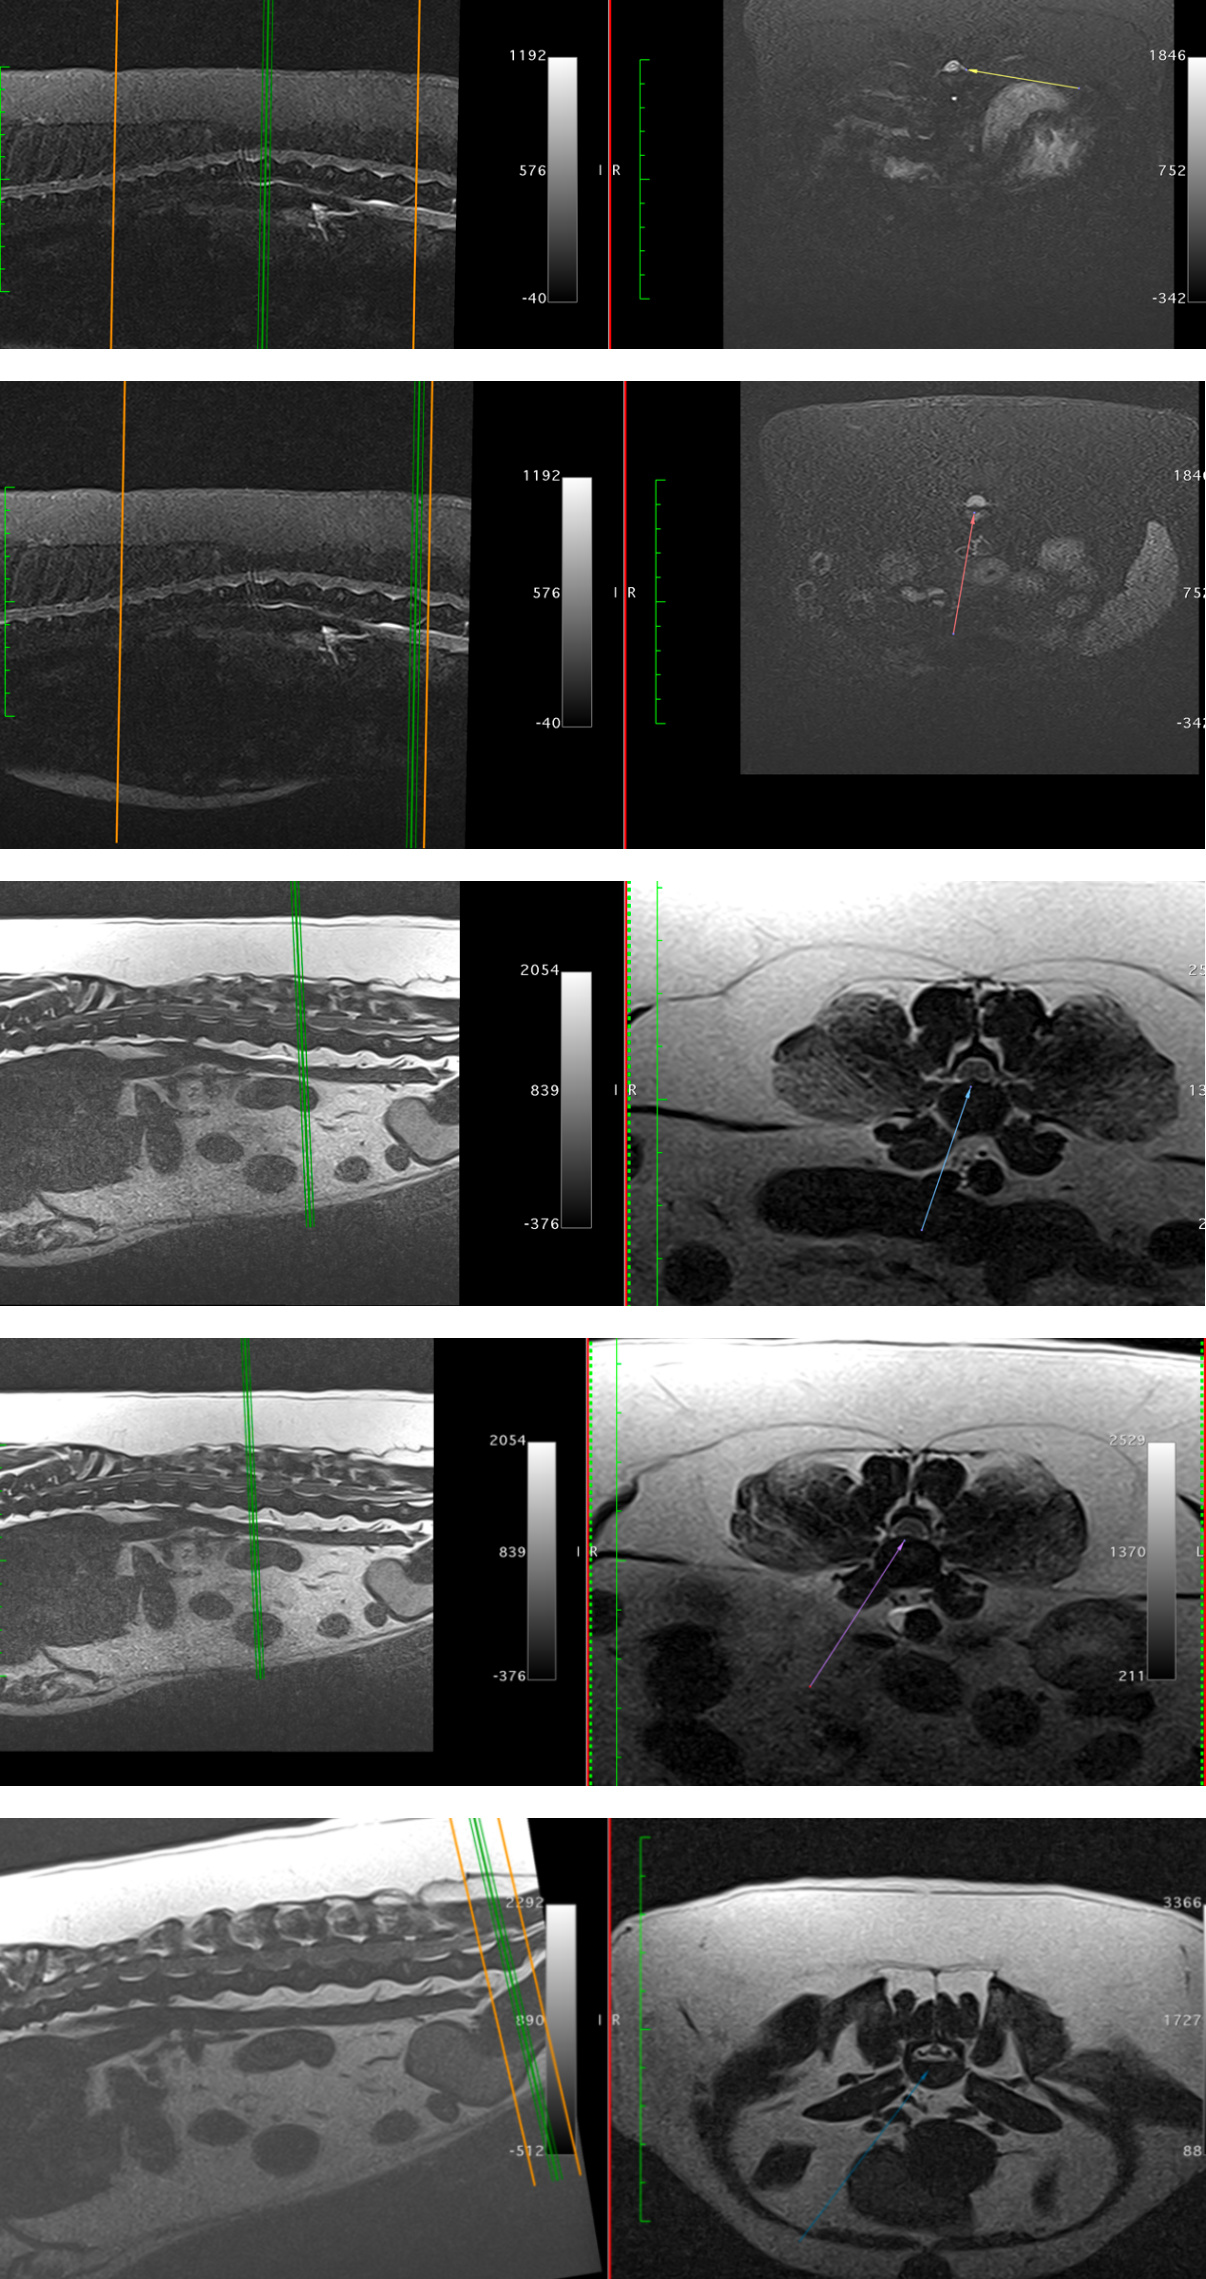

2月18日,lucky做了mri,检查结果是多个椎间盘中度突出,C7-T1、T12-T13,L2-L3、L3-L4、L7-S1(C:颈椎、T:胸椎 、L:腰椎、S:荐椎)。

诊断为多脊椎的椎间盘突出(ivdd4级)影像如图。

MRI影像如图所示